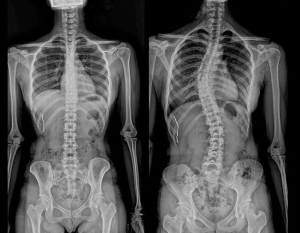

척추측만증은 우리가 말하는 허리, 즉 척추가 휘어진 현상을 말합니다.

척추측만증을 진단할 때 일반적으로 cobb's 각도를 사용합니다.

콥스각도가 8도~10도까지는 정상으로 보며 그 이상을 척추측만증으로 판단하며 20도~30도 휘어짐이 큰 각도는

병원치료가 필요한 단계로 볼 수 있습니다.